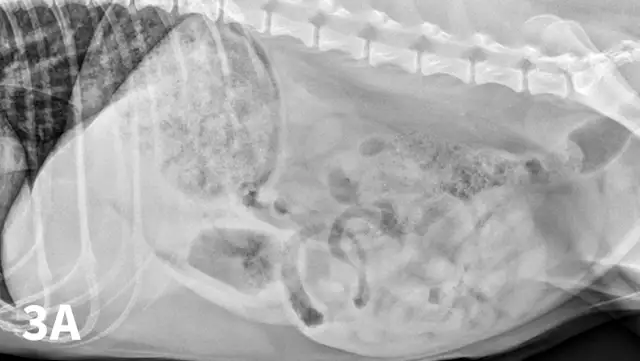

Radiographic features of small intestinal mechanical obstruction depend on its completeness, location, and duration.2 Whereas metallic FBs or those with mineral content are easily recognized within the GI lumen (Figure 1), nonmineralized, nonmetallic objects (eg, cloth) within the GI tract are more difficult to identify (Figure 2). Some may be recognized by their geometric shape. The most consistent sign of mechanical obstruction is variable dilation of intestinal loops proximal (orad) to the obstruction (described as a mixed population of small intestine; Figure 2). Determination of small intestinal diameter can be made by comparing it to the L5 vertebral body height in dogs.3 Values greater than 1.6 are suggestive of obstruction (Figure 2A). In cats, a ratio of the maximum small intestinal diameter to vertebral end plate height of L2 greater than 4 indicates a high likelihood of intestinal obstruction.4

Qualitative assessment of intestinal size by experienced clinicians may be as accurate in determining the presence of mechanical obstruction as calculation of ratios. Obstructed intestine usually contains fluid and gas; however, if the obstruction is orad, reflux into the stomach can occur and limited intestinal distension may be apparent. More distal (aborad) or more complete obstruction leads to greater dilation. Stacking of intestinal loops occurs with more severe dilation as segments become increasingly crowded in a relatively smaller space (Figure 2B).

Right lateral (A) and VD (B) abdominal radiographs of a Labrador retriever with an obstructive ileus. A FB (sock) is present within a dilated small intestinal loop in the right caudoventral abdomen (arrows). The dashed lines outline a fluid-filled loop measuring 2.7 cm and a gas-filled loop measuring 2.4 cm, compared to the height of L5 (Asolid line, 1.1 cm);  the resulting ratios of 2.4 and 2.2, respectively, are much greater than the upper limit of 1.6 for normal small intestine to L5 height ratio. Several stacked gas-filled loops of small intestine are present in the left midabdomen (B).